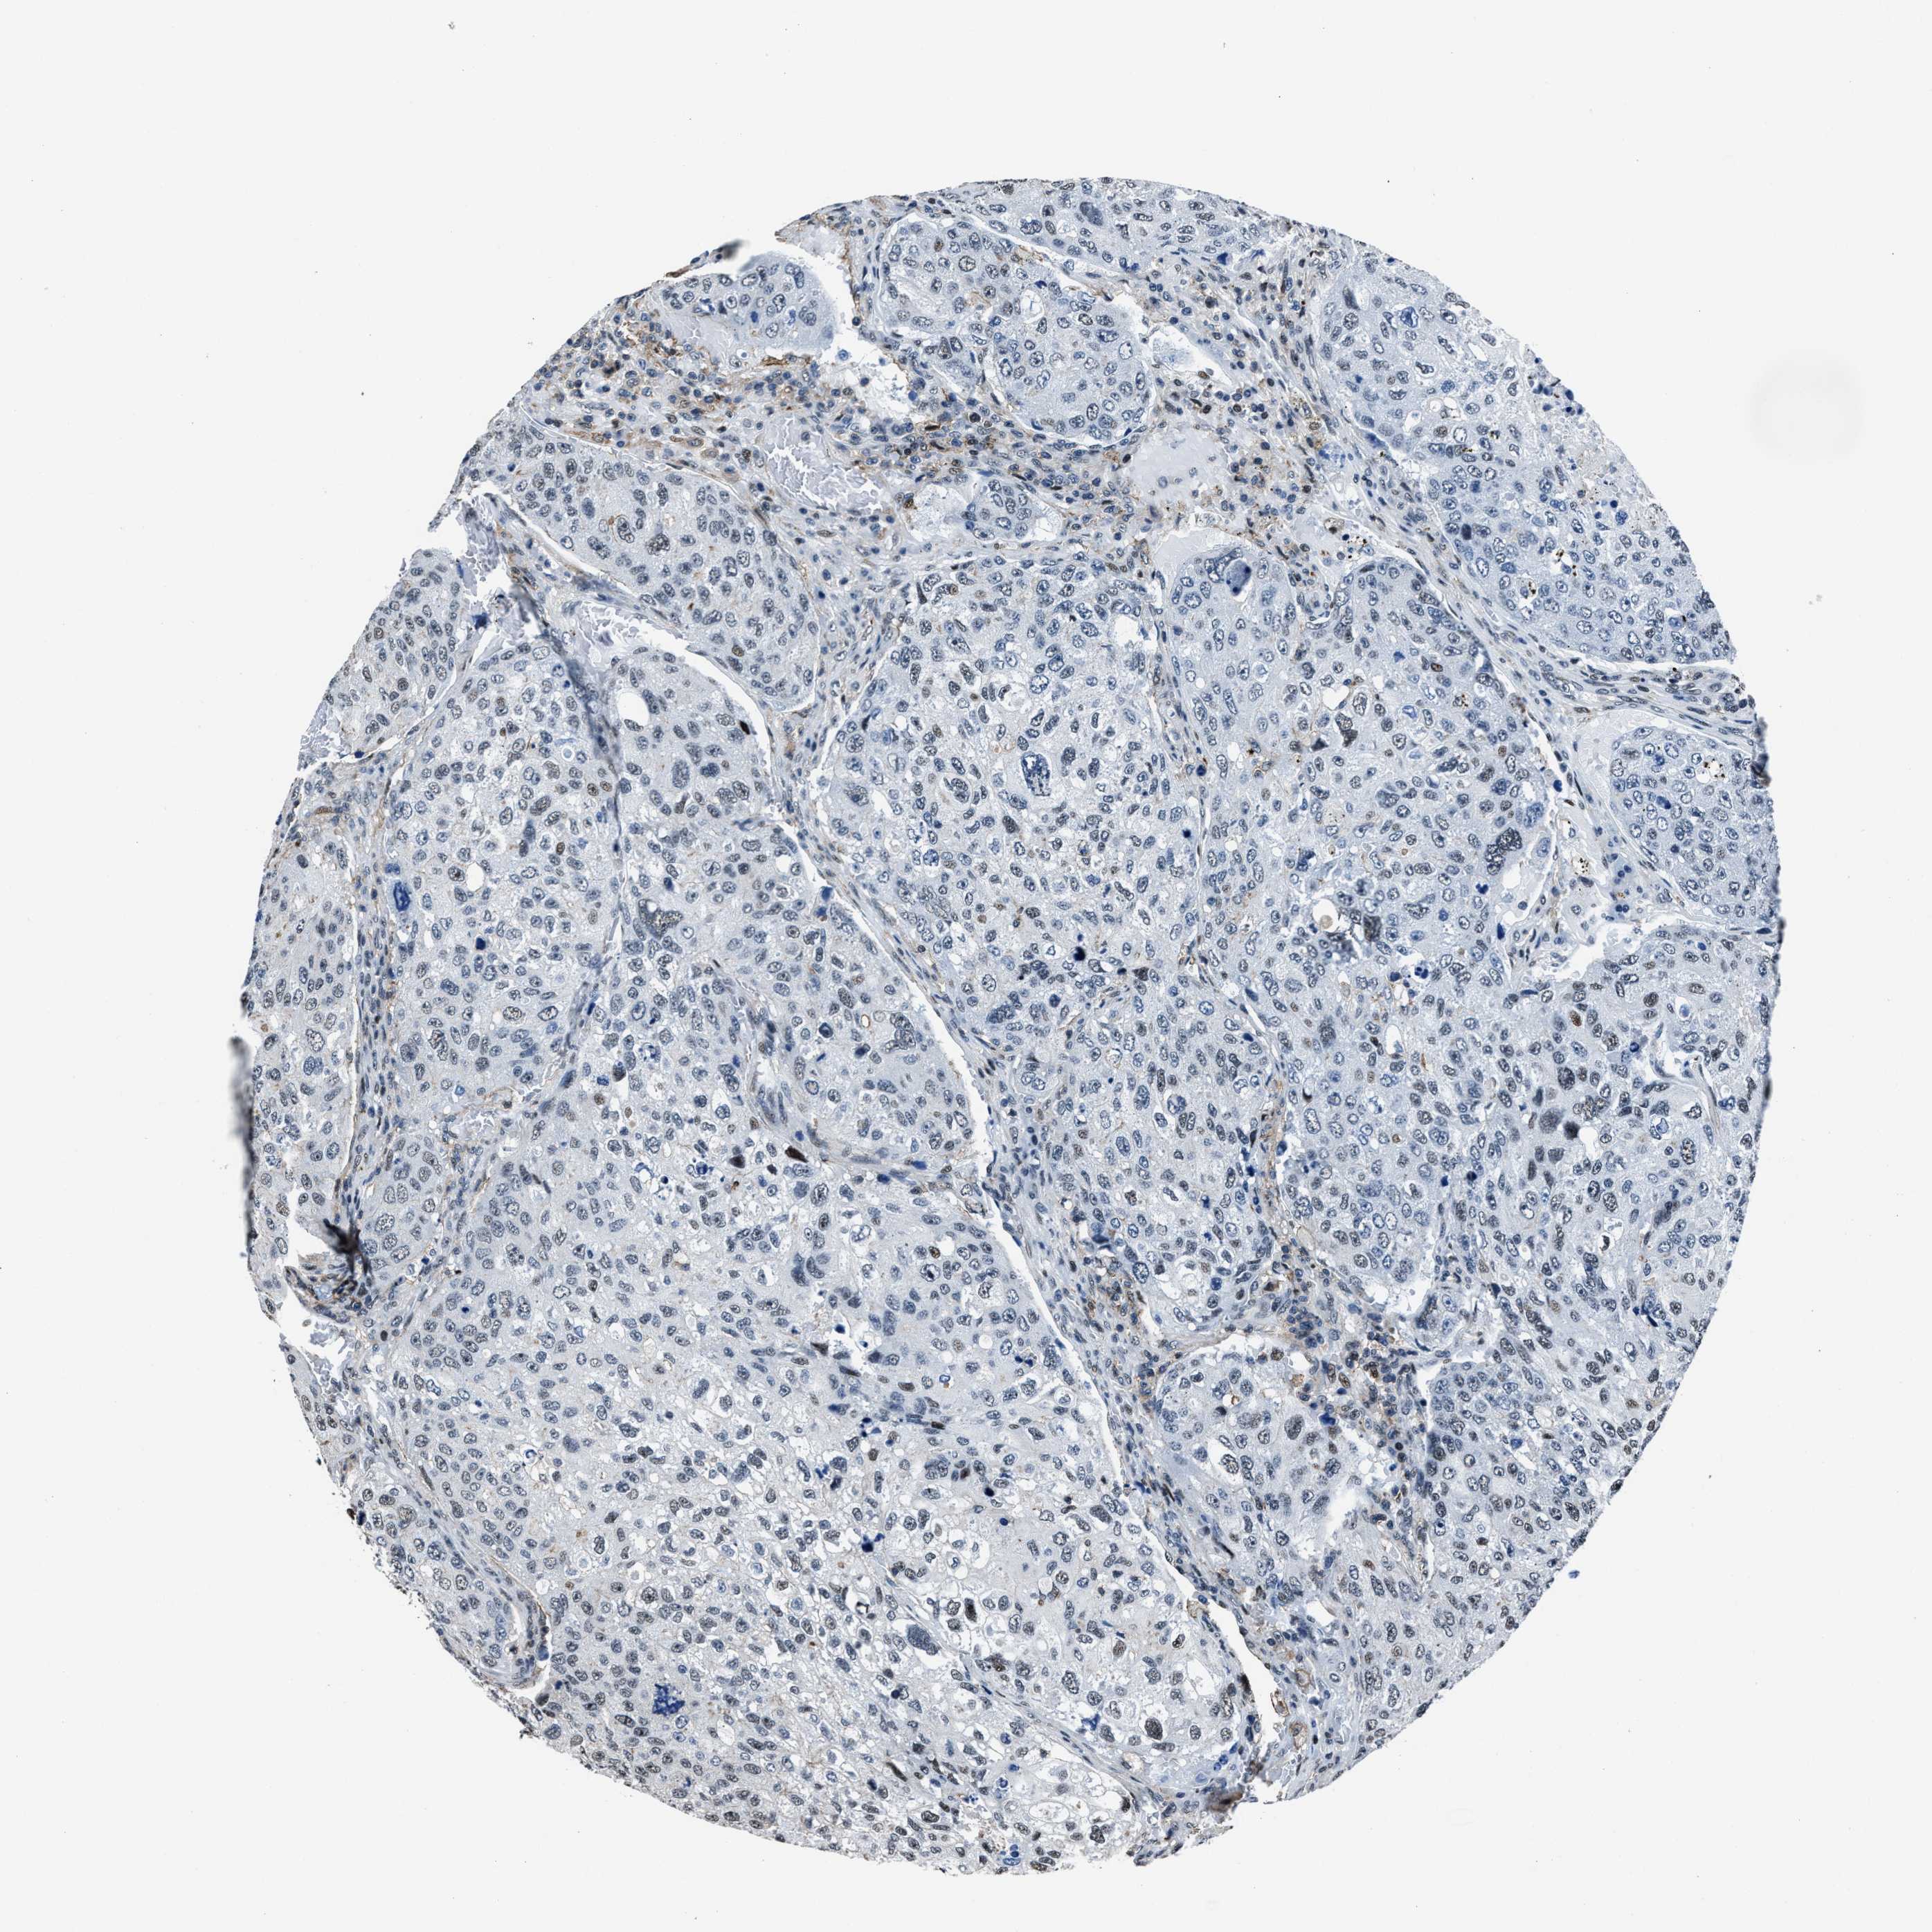

UROTHELIAL CANCER - Protein expressioni

A mouse-over function shows sample information and annotation data. Click on an image to view it in a full screen mode. Samples can be filtered based on level of antibody staining by selecting one or several of the following categories: high, medium, low and not detected. The assay and annotation is described here.

Note that samples used for immunohistochemistry by the Human Protein Atlas do not correspond to samples in the TCGA dataset.

Antibody stainingi

Antibody staining in the annotated cell types in the current human tissue is reported as not detected, low, medium, or high, based on conventional immunohistochemistry profiling in selected tissues. This score is based on the combination of the staining intensity and fraction of stained cells.

Each image is clickable and will lead to virtual microscopy that enables deeper exploration of all samples and also displays staining intensity scores, fraction scores and subcellular localization as well as patient and tissue information for each sample.

Antibody HPA020131

Staining

High

Medium

Low

Not detected

Intensity

Strong

Moderate

Weak

Negative

Quantity

>75%

75%-25%

<25%

None

Location

Urothelial carcinoma, Low grade

Urothelial carcinoma, High grade